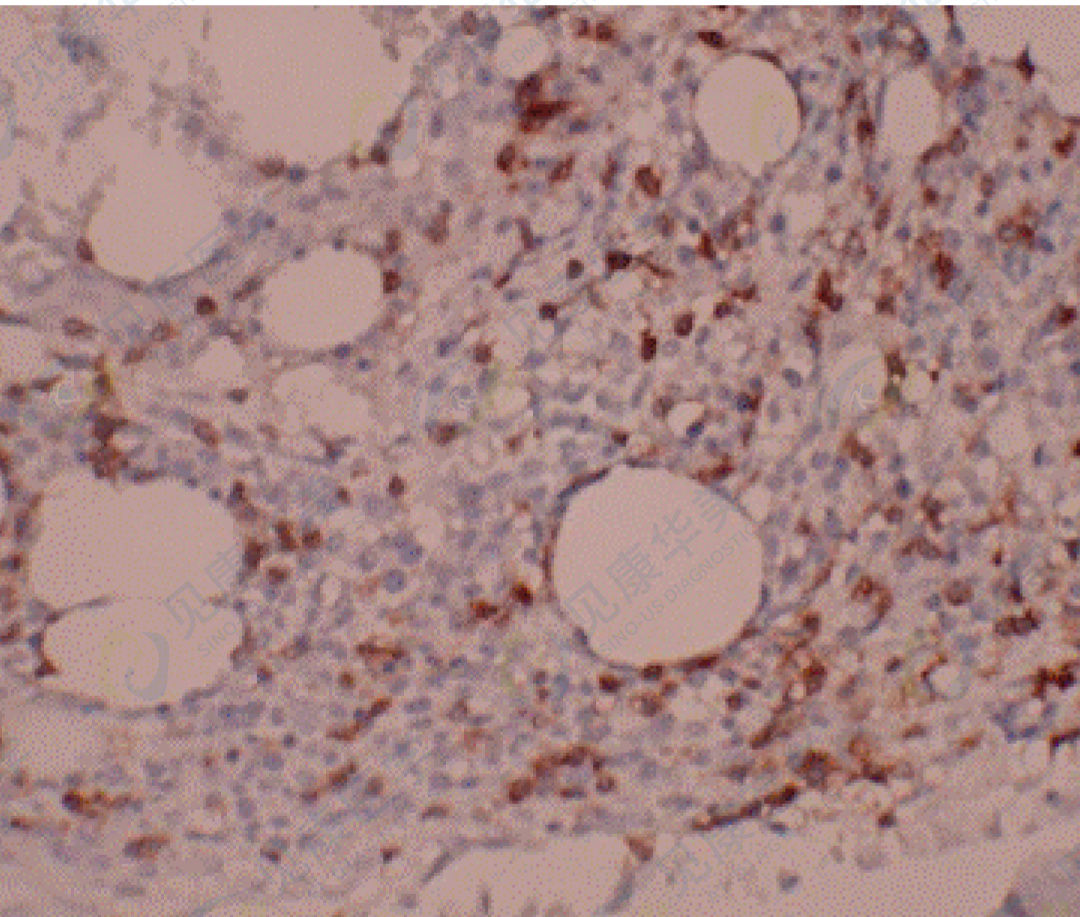

ATLL骨髓活检中少量肿瘤细胞浸润(免疫组化CD3染色)